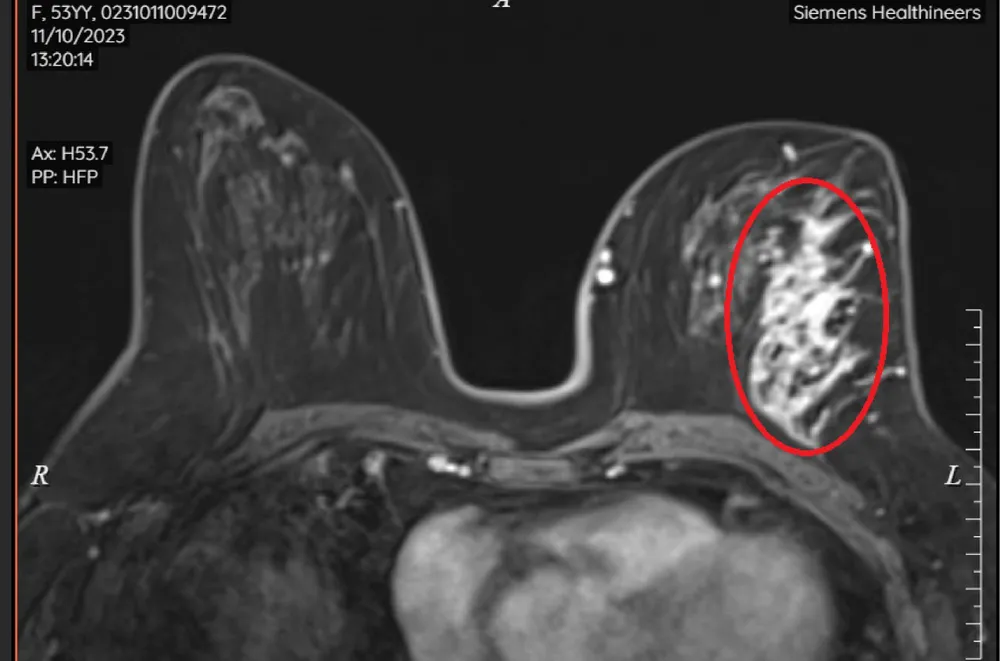

Kết quả chụp MRI vú cho thấy rõ tổn thương không tạo khối 1/4 trên ngoài với tính chất ngấm thuốc mạnh (Birads 5) rất nghi ngờ ác tính. Dựa vào hình ảnh MRI, kết hợp đối chiếu siêu âm, bệnh nhân được tiến hành sinh thiết lõi dưới siêu âm, cuối cùng ghi nhận ung thư ống tuyến vú tại chỗ.

MRI sau tiêm thuốc có hình ảnh tổn thương không tạo khối, ngấm thuốc mạnh 1/4 trên ngoài vú trái. |